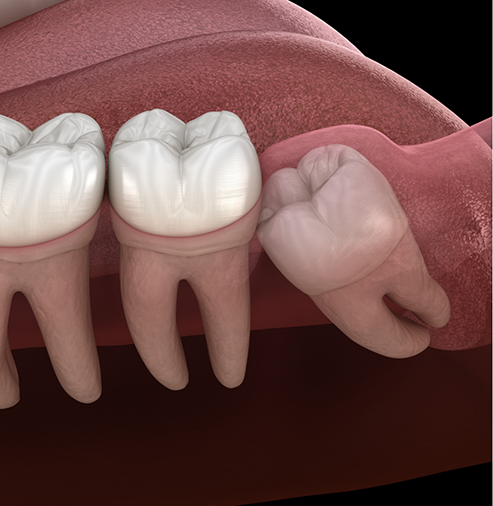

Your wisdom tooth extraction procedure can vary based on whether your third molars are impacted below the gumline or if they have fully erupted. For impacted teeth, we may refer you next door to the expert oral surgeon that we collaborate with to offer our patients outstanding results and truly professional care. This would involve the surgical removal of the wisdom teeth by creating a window in the gumline and removing them.

For simpler extractions, like in cases where the teeth have completely come in, Dr. Mazhari can gently lift the wisdom teeth out of their sockets and remove them from the gumline. This process doesn’t require any surgical intervention, and to make sure that you remain completely comfortable, we’ll administer a localized anesthesia to numb the area.